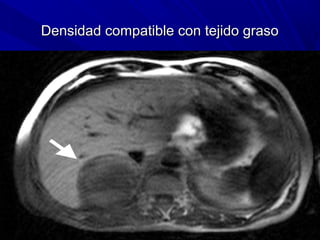

MIELOLIPOMA ADRENAL (RM)

Densidad compatible con tejido graso